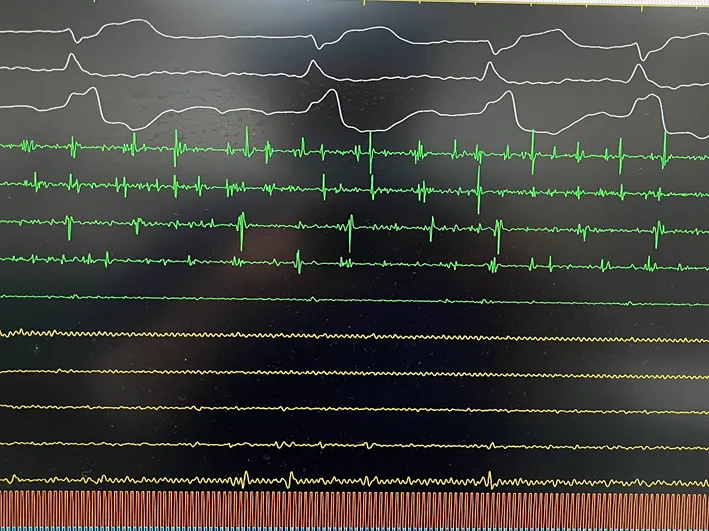

手术在全麻下进行,消融策略涵盖双侧肺静脉、左房后壁及上腔静脉,总计消融73个位点,累计消融时间仅146秒。术中活化凝血时间(ACT)维持在250-300秒,未出现并发症。消融结束后,患者仍为房颤心律,经电复律成功转为窦性心律,手术顺利完成。

LSPV消融及前后电位对比

LIPV消融及前后电位对比

RSPV消融及前后电位对比

RIPV消融及前后电位对比

后壁消融及前后电位对比

上腔静脉消融及前后电位对比